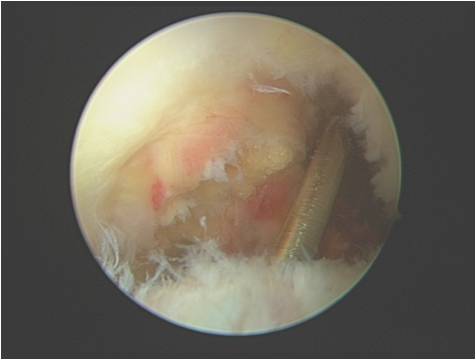

髋关节镜手术